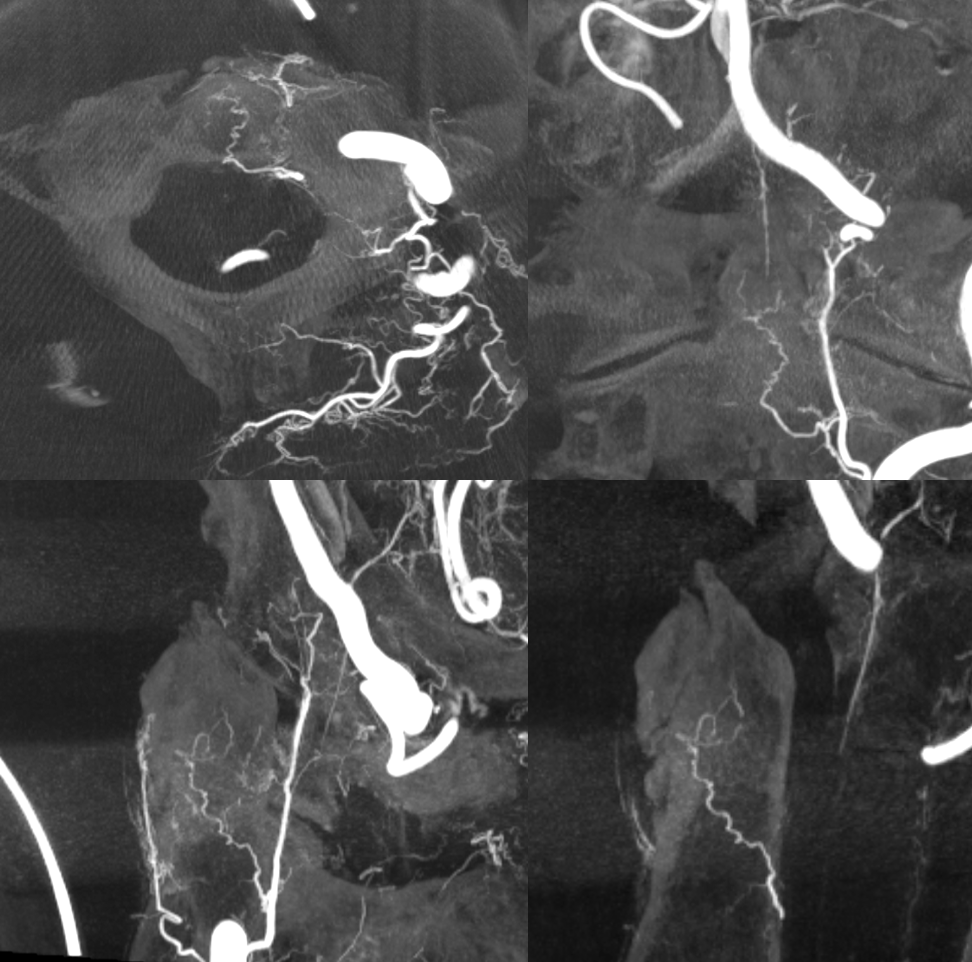

Many cases, like the one above, are derived from embolization of meningiomas, allowing for subselective odontoid catheterizations. Below are fusion DYNA CT images of this case, showing the target lesion. Most of the supply is derived from hypoglossal division, seen via the green-colored left ECA injection. The vert injection is in red, opacifying the arcade among everything else vertebrobasilar.

Another case — cone beam CT is great of course for odontoid arcade and most everything else. Left vert injection opacifies the odontoid arcade (arrows) and its supply to C2 bone (dashed arrows). Note also excellent visualization of both anterior spinal artery territory (white oval) and very prominent posterior / lateral spinal region (dashed white oval)

The same case, now with microcatheter position in the odontoid arcade. The same supply to the bone is noted, however note complete lack of spinal cord or radicular artery visualization. Direct spinal cord supply from the odontoid arcade is exceptionally rare, making it a relatively good embolization position in what is still a very treacherous area.

Fusion of two vertebral artery Cone Beam CT injections demonstrating both odontoid arcades (solid green and red arrows), and the intersegmental epidural connections between them (dashed arrows). At the apex of the arcade, supply to the ligamentous / adipose tissues around the dens is also present (arrowheads)